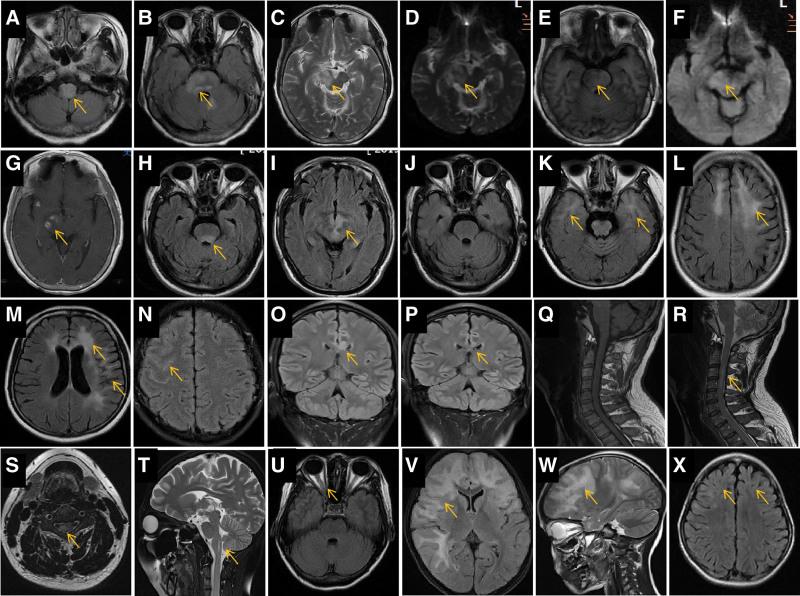

Myelin oligodendrocyte glycoprotein (MOG) antibody-associated disease (MOGAD) is an immune-mediated inflammatory demyelinating disease of the central nervous system. This study aimed to delineate the clinical manifestations, imaging features, and long-term outcomes in Chinese patients with MOGAD and analyze the recurrence-associated factors. The phenotypic and neuroimaging characteristics of 15 Han Chinese patients with MOGAD were retrospectively analyzed. Demyelinating attacks, MOG antibodies in the cerebrospinal fluid/serum, response to immunotherapy, follow-up outcomes, and recurrence-associated factors were recorded. The median age at disease onset was 34 years (range, 4-65 years). The most common initial presentations included vision loss (10/15, 66.7%) and seizures (5/15, 33.3%). Serum MOG-Ab titers in 14/15 cases were higher than those in the cerebrospinal fluid and were detected in 3/6 relapsed patients. Brain magnetic resonance imaging during acute attacks showed lesions in 10/15 patients (66.7%), mostly in the cortex/subcortical white matter (5/15, 33.3%). Recurrence occurred in 6/15 patients (40.0%); in 4 patients, recurrence occurred shortly after immunotherapy discontinuation. Residual neurological deficits were present in 5/15 patients (33.3%), including visual impairment, incapacitation, cognitive impairment, and speech reduction. Optic neuritis was the most common clinical manifestation of MOGAD. magnetic resonance imaging findings were heterogeneous and the cerebral cortex/subcortical white matter was the most susceptible brain region. Although patients in the acute phase responded well to methylprednisolone pulse therapy, the long-term recurrence rate was high. Consistently detected serum MOG antibodies and inappropriate maintenance immunotherapy may be associated with recurrence, and residual neurological deficits should not be ignored.